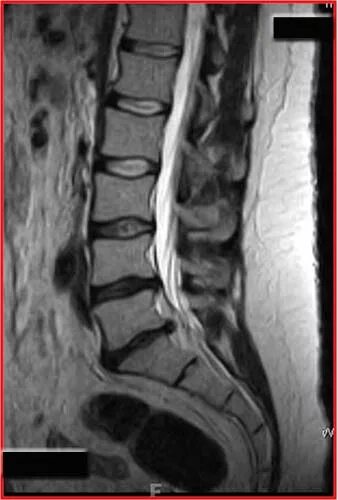

Протрузия дисков l2